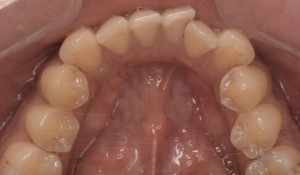

CASE 11

Before

After

基本情報

| 年齢・性別 | 32歳・男性 |

|---|---|

| 主訴 | 歯石をとりたい |

| 治療内容 | スケーリング |

| 治療期間 | 30分 |

| 治療費 | 1,500円(保険診療) |

| リスク・副作用 | 知覚過敏、歯肉退縮、出血 |

| 治療方針 | 今後も定期的にクリーニングを行っていきます。 |